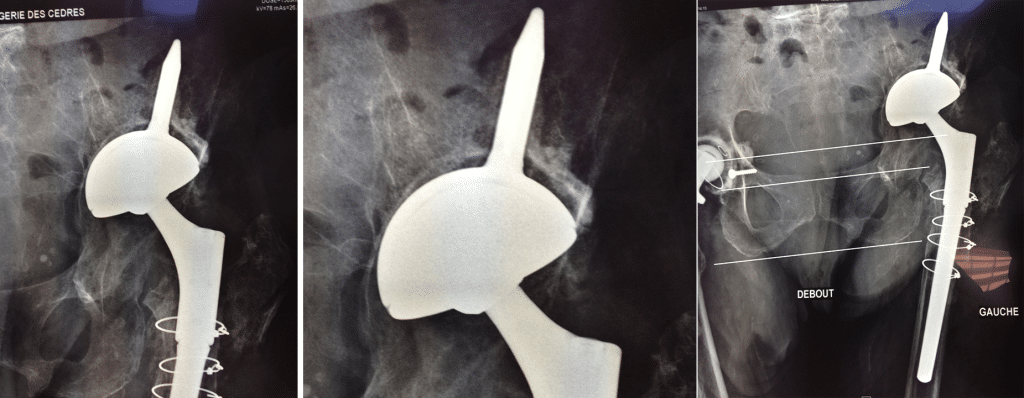

Le scanner confirmait le présence d’une poutre ilio ischiatique compatible avec l’utilisation du cotyle INTEGRA™.

Effet “jumbo cup ” (56) , ascension et appui sur la corticale du toit du néocotyle.

Pivot fémoral Press Fit sans ciment.